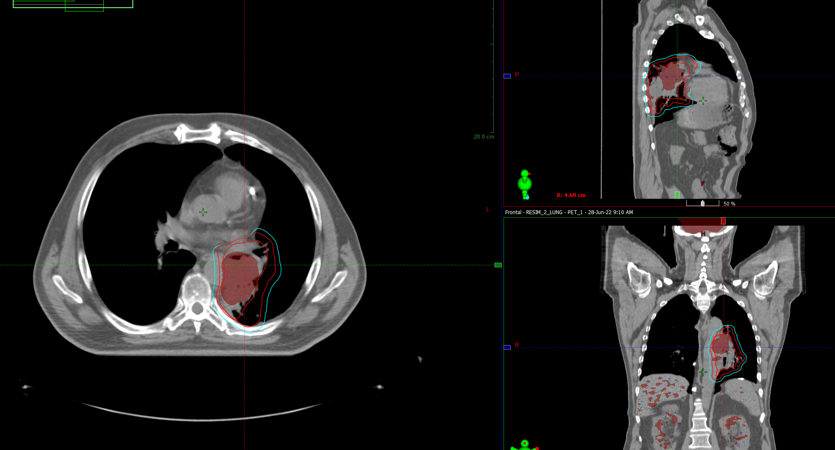

По данным ПЭТ-КТ с 18-ФДГ от 28.06.2022г. по сравнению с исследованием от 29.03.2022г. отмечается:

- уменьшение размеров с некоторым повышением метаболической активности образования в воротах левого легкого;

- уменьшение размеров и снижение метаболической активности медиастинальных лимфоузлов.

В воротах левого легкого сохраняется метаболически активный опухолевый узел с вовлечением главного, нижнедолевого, частично верхнедолевого бронхов, с некоторым уменьшение размеров и ростом метаболической активности, общими размерами около 60х38 мм SUVmax=24,72 (ранее до 83 мм в аксиальной проекции и до 81 мм в краниокаудальной проекции, SUVmax=21.41). Опухоль располагается на расстоянии около 30 мм от киля трахеи с вовлечением левой легочной артерии (обхват около 50%) и тесным прилеганием к нисходящей аорте. В правом легком очаговая и инфильтративная патология легких не определяется.Уменьшение размеров и снижение метаболической активности медиастинальных лимфоузлов, наибольшими размерами/накоплением РФП: подкаринальной группы (7) до 7 мм SUVmax=3,32 (ранее 10 мм, SUVmax=7.49); субаортальной группы (5) до 4 мм SUVmax=2,64 (ранее 8 мм, SUVmax=4.70). Лимфоузлы ворот левого легкого до 7 мм SUVmax=4,36 (ранее сливались с образованием).

В воротах левого легкого сохраняется метаболически активный опухолевый узел с вовлечением главного, нижнедолевого, частично верхнедолевого бронхов, с некоторым уменьшение размеров и ростом метаболической активности, общими размерами около 60х38 мм SUVmax=24,72 (ранее до 83 мм в аксиальной проекции и до 81 мм в краниокаудальной проекции, SUVmax=21.41). Опухоль располагается на расстоянии около 30 мм от киля трахеи с вовлечением левой легочной артерии (обхват около 50%) и тесным прилеганием к нисходящей аорте. В правом легком очаговая и инфильтративная патология легких не определяется.Уменьшение размеров и снижение метаболической активности медиастинальных лимфоузлов, наибольшими размерами/накоплением РФП: подкаринальной группы (7) до 7 мм SUVmax=3,32 (ранее 10 мм, SUVmax=7.49); субаортальной группы (5) до 4 мм SUVmax=2,64 (ранее 8 мм, SUVmax=4.70). Лимфоузлы ворот левого легкого до 7 мм SUVmax=4,36 (ранее сливались с образованием).

Пациенту рекомендован курс химиолучевой терапии на опухоль легкого и ПЭТ позитивные лимфатические узлы РОД 2Гр до СОД 60Гр на фоне еженедельного введения химиотерапии по схеме карбоплатин + паклитаксел

13.07.2022 выполнена КТ- топометрия органов грудной клетки с толщиной среза 2.5 мм.

Выполнено оконтуривание на КТ срезах объемов мишени (GTV,CTV,PTV) и всех органов риска